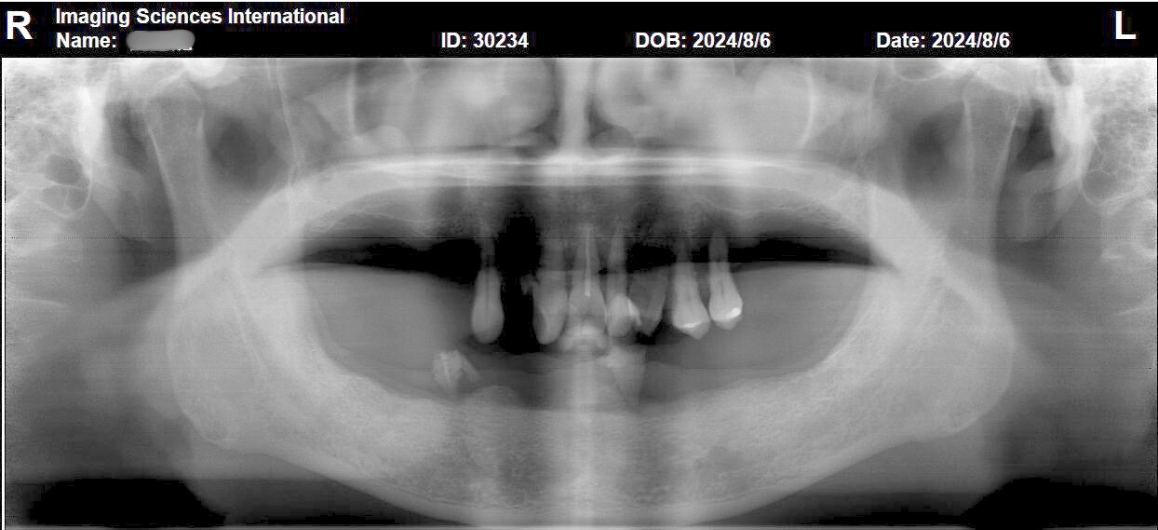

經術前影像檢查(如下圖)可發現,上顎部分的齒質狀況不佳,已無保留價值;下顎部分則有廣泛性牙周病,剩餘牙根已無法乘載生理性咬合力。醫師評估過後,決定先為他做All-on-4數位植牙,之後再進行全口重建,徹底改善他的口腔問題。

張正忠醫師先替患者進行All-on-4數位植牙手術,透過數位手術導板,在他的下顎前牙與小臼齒區段,均勻植入4支植體(如下圖),其中的後側兩支植體,採傾斜植入,增加力學支點寬度,減少補骨需求。